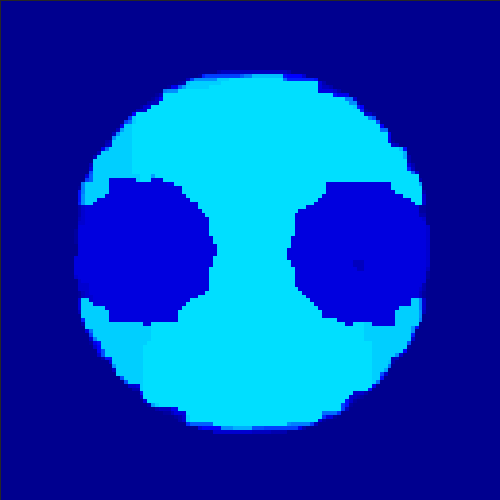

5.2 Monte Carlo Simulation

In order to test the behaviour of the proposed method in a more realistic, random-based test case, we performed a Monte Carlo simulation for dynamic SPECT imaging. First, we created a simple image phantom consisting of an outer and two inner circles which represents the structure of the region of interest (see figure 8(a)). Within those regions we assumed concentration curves over a time period of 90 time steps as displayed in figure 8(b). Based on the tracer intensity in an image frame at each time step, we created a variable number of random decay events (where the number is proportional to the average concentration in one pixel in the whole image frame per time step) with a probability proportional to the concentration in every subregion. They are detected by a virtual double head gamma camera rotating around the patient by 46 degrees per time step, which consists of 374 detector bins. Every simulated decay event is projected onto the scanner and counted by the corresponding detector bin.

In two different tests we fixed the number of events counted by the detector equal to (resp. ) times the average concentration in one pixel. The resulting sinogram images of the accumulated counts in each bin are shown in figure 9.

Based on the sinogram data we applied the proposed algorithm in order to reconstruct the original image sequence. The results for both test cases are shown in figure 10.

As one can see, the method is able to reconstruct the regions properly, even in case of a low count number. Within a number of iterations (average of 100 outer and 10000 inner iterations), the algorithm presents a reasonable reconstruction of the region of interest and the corresponding regional tracer concentration curves. Here, the parameters were not optimized as in the case of the synthesized data sets in the previous section, but kept fixed as , and . With futher optimized parameter values one could possibly provide even better results.